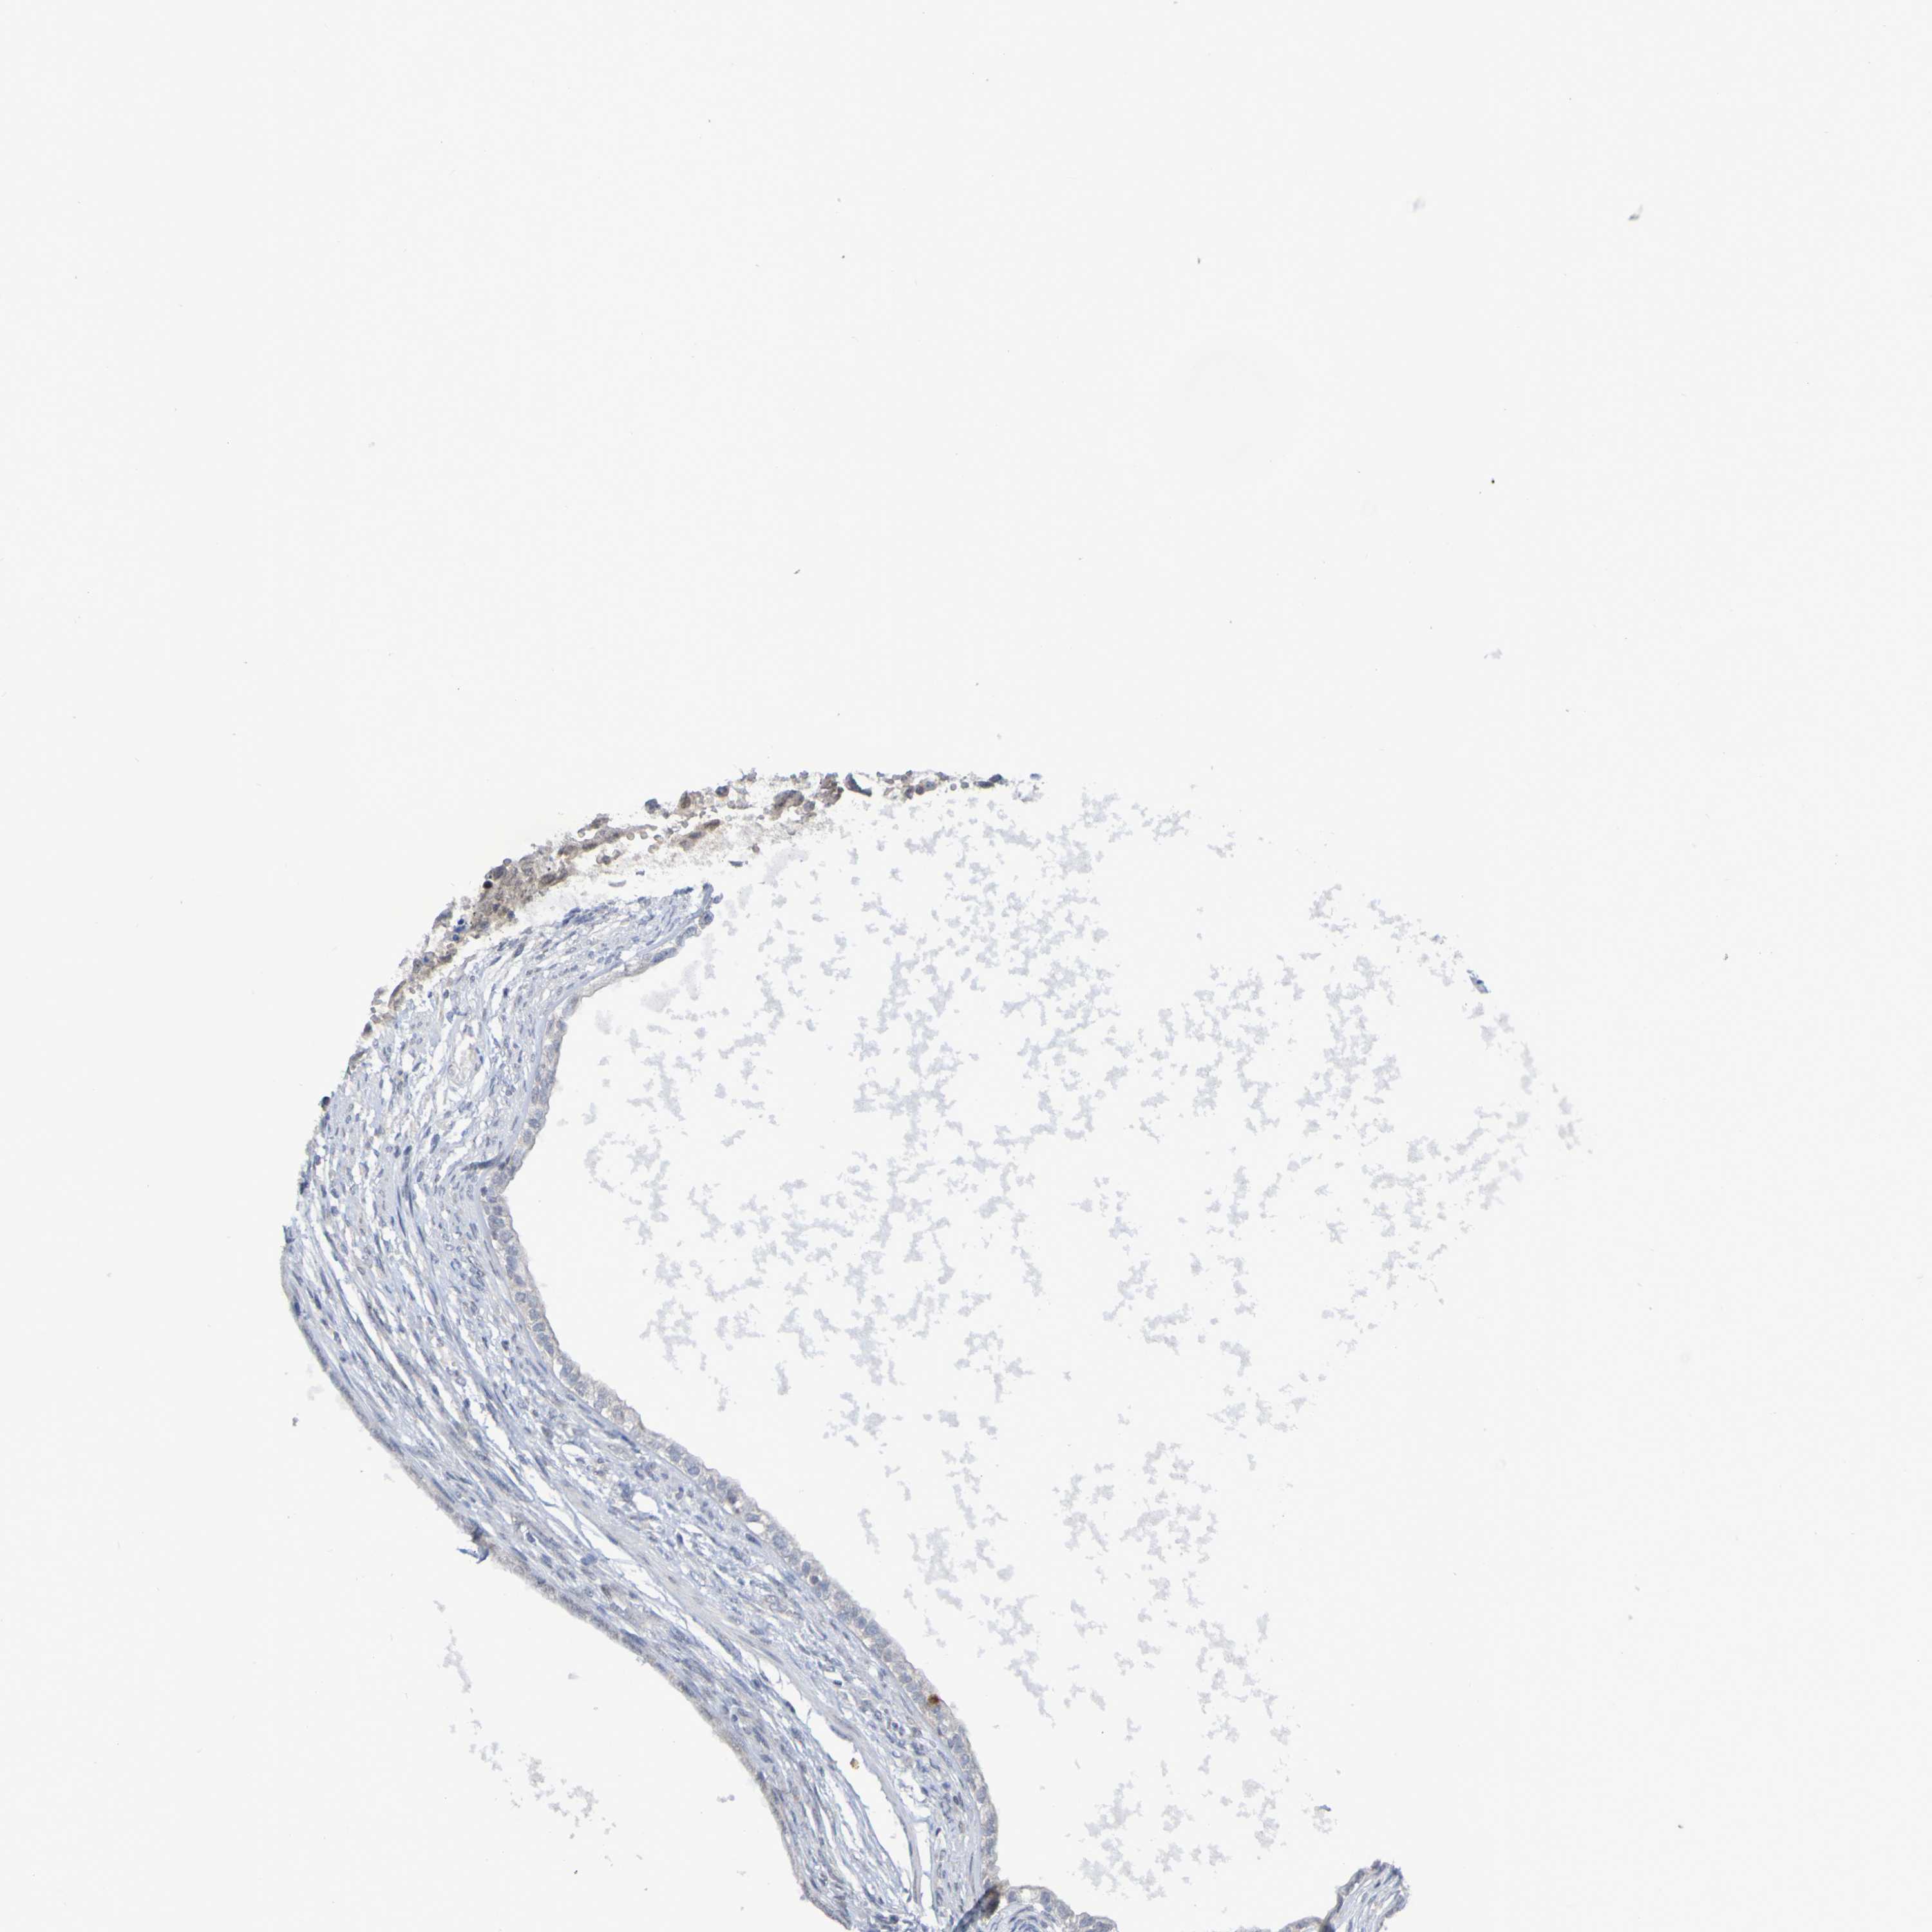

TESTIS CANCER - Protein expressioni

A mouse-over function shows sample information and annotation data. Click on an image to view it in a full screen mode. Samples can be filtered based on level of antibody staining by selecting one or several of the following categories: high, medium, low and not detected. The assay and annotation is described here.

Note that samples used for immunohistochemistry by the Human Protein Atlas do not correspond to samples in the TCGA dataset.

Antibody stainingi

Antibody staining in the annotated cell types in the current human tissue is reported as not detected, low, medium, or high, based on conventional immunohistochemistry profiling in selected tissues. This score is based on the combination of the staining intensity and fraction of stained cells.

Each image is clickable and will lead to virtual microscopy that enables deeper exploration of all samples and also displays staining intensity scores, fraction scores and subcellular localization as well as patient and tissue information for each sample.

Antibody HPA063275

Antibody HPA067326

Antibody CAB012652

Seminoma, NOS

Carcinoma, Embryonal, NOS

Teratoma, malignant, NOS